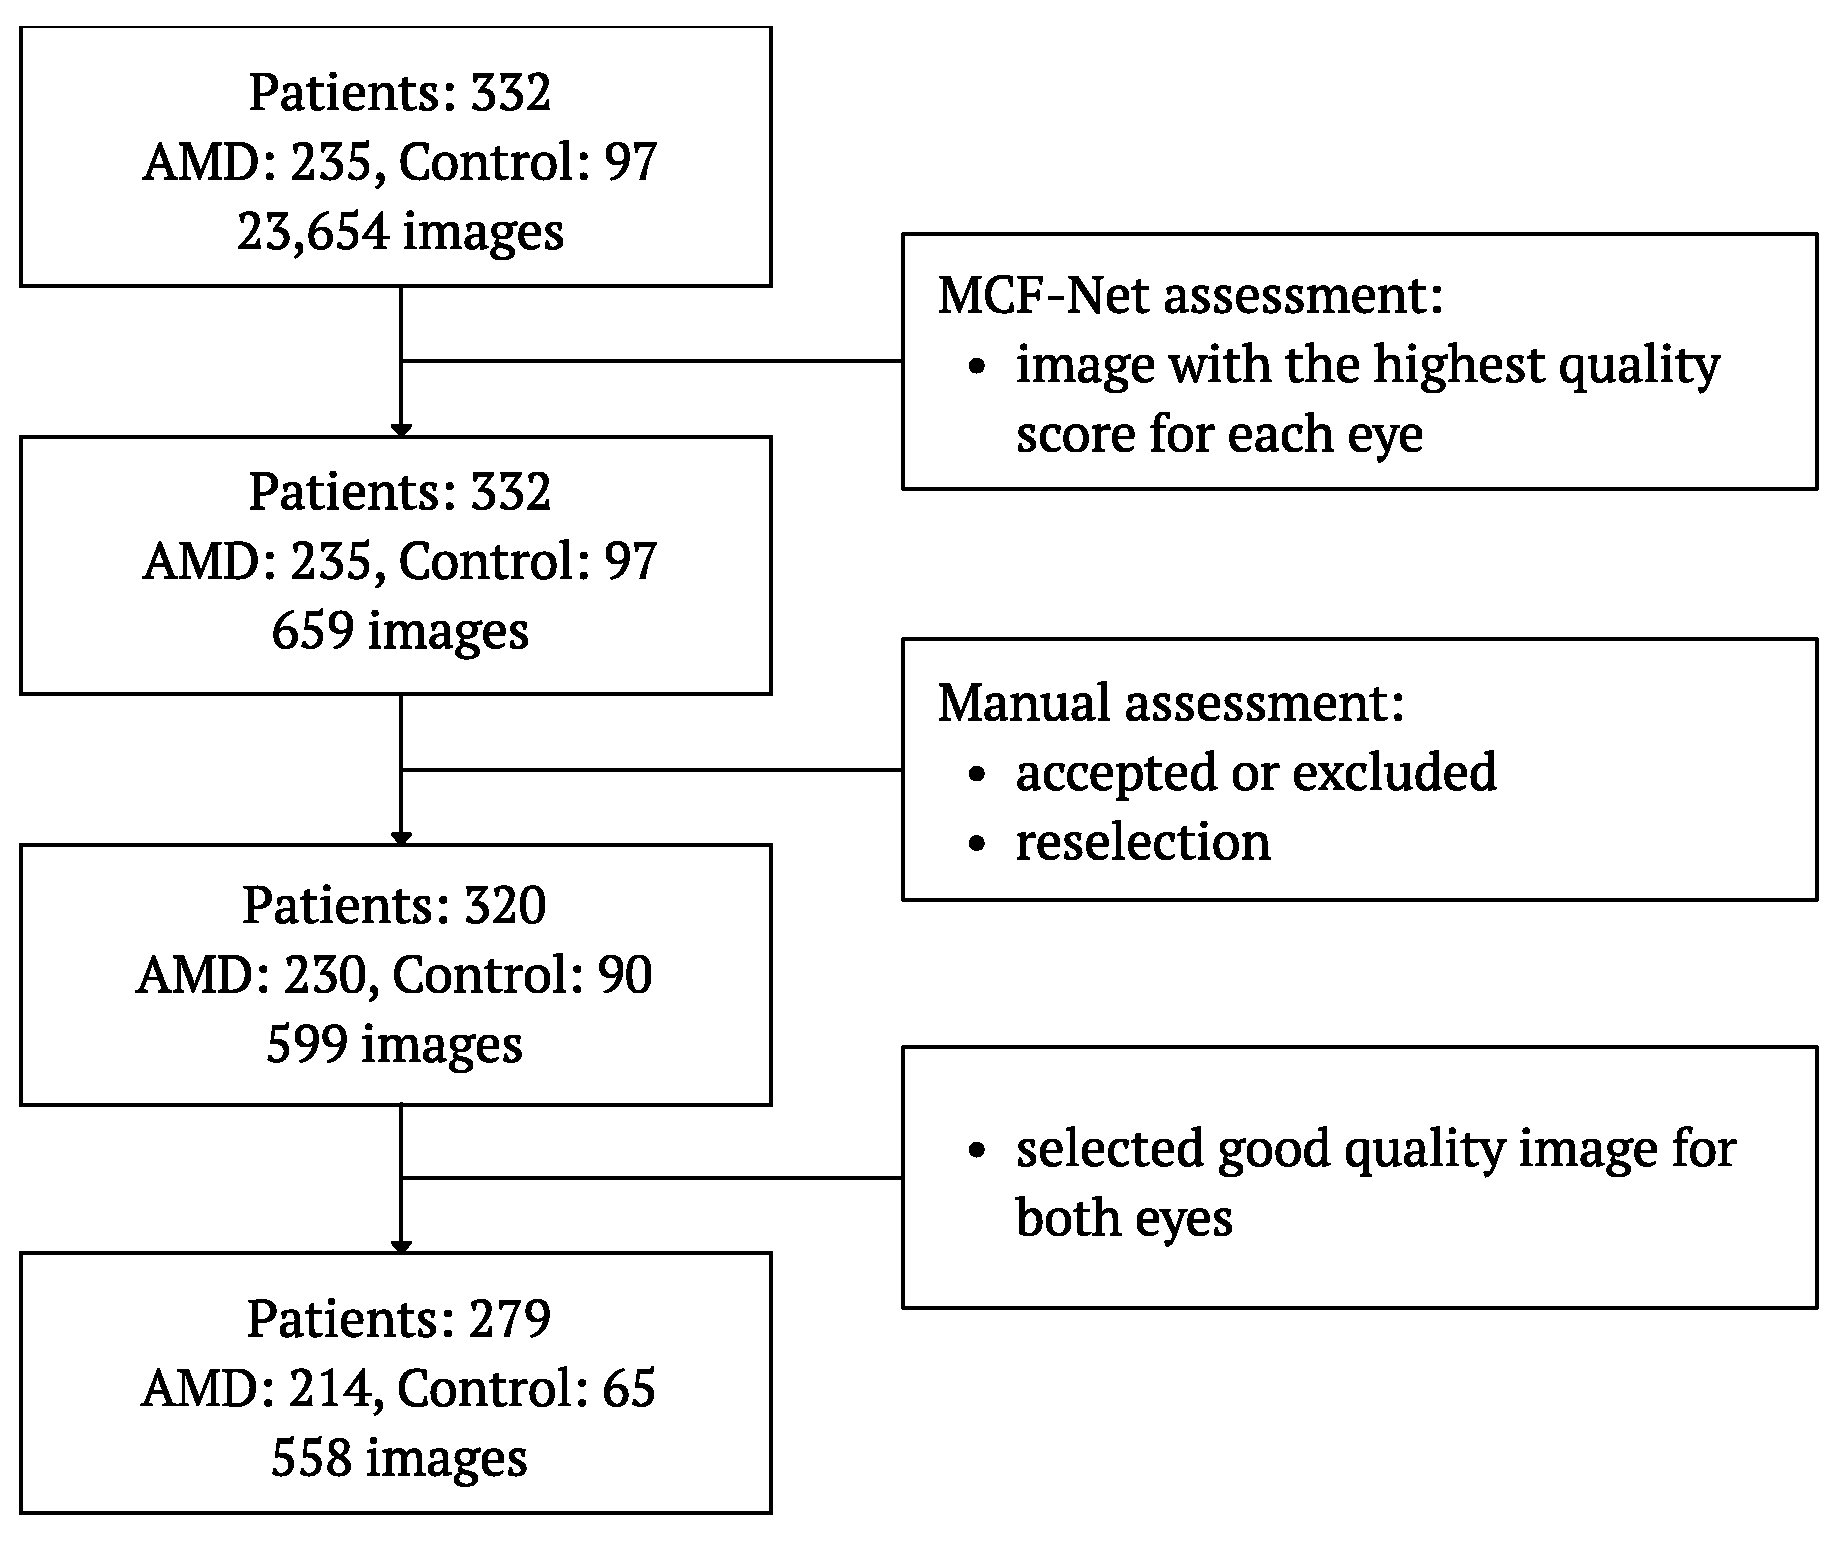

2.6. Fundus Images Selection

2.7. Deep Learning